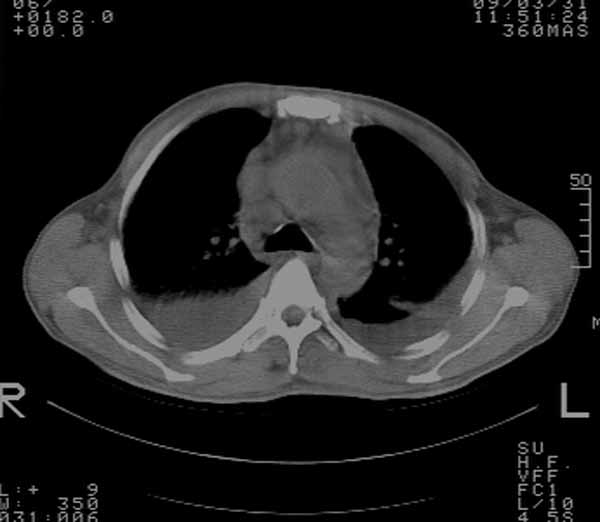

以下是引用余辉在2009-3-31 18:43:00的发言:[br]肺水肿,双侧心腔积液,心包积液,心影增大,疑似心衰

以下是引用wangyong1977在2009-3-31 20:46:00的发言:[br]肺水肿,双侧胸腔积液,心包积液,心影增大,疑似心衰 [br]

以下是引用宇宙ct在2009-3-31 18:57:00的发言:[br]肺水肿,双侧心腔积液,心包积液,心影增大,疑似心衰 [br] [br]